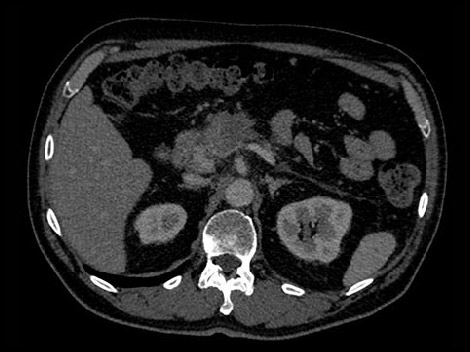

In this hypothetical example, the radiologists need more information about a visible mass in the pancreas in order make a confident diagnosis.

With a traditional CT, if the image is inconclusive, the patient may be asked to return for an additional scan.

Unlike traditional CT images, spectral-detector CT images capture spectral information 100% of the time —without special planning or set-up. That means you can analyze the spectral data in any image retrospectively, using a variety of spectral viewing tools. You can, for example, adjust the monoenergetic level or get Zeffective maps. Try it yourself below.